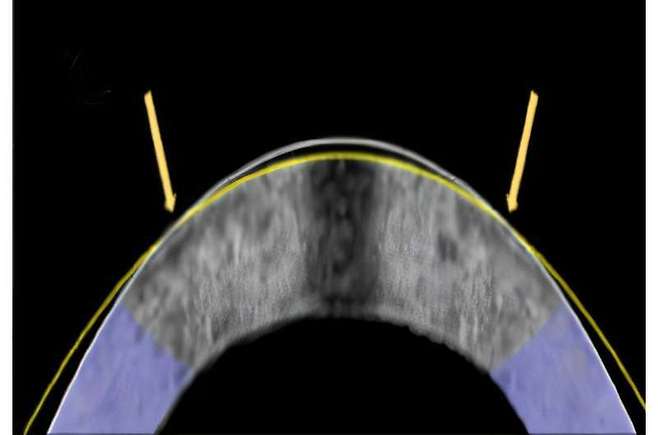

의학전문 매체 메디컬익스프레스에 따르면 연구팀은 이 원리를 이용해 특수 제작한 백금 전극 렌즈를 토끼 눈에 올려 실험했다. 렌즈는 ‘교정된 각막 곡률’을 미리 설계해 놓은 틀이었고, 여기에 미세한 전기신호를 가하자 단 1분 만에 각막이 렌즈 모양대로 바뀌었다. 즉, 레이저로 깎지 않고도 각막 성형에 성공한 것이다.